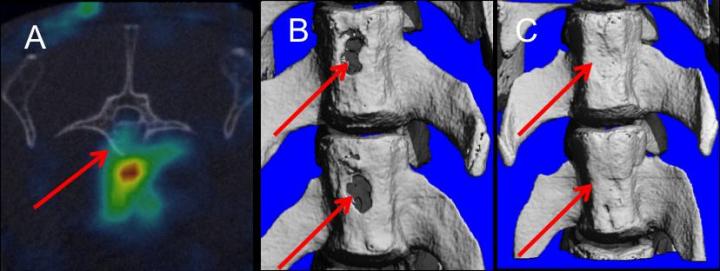

Bone regeneration in vertebral defects was monitored at several different times after surgery by performing Computed Tomography, a computerized X-ray scanner that creates cross-sectional pictures of internal organs, bones and other structures.

"We saw increased bone volume density and healthy bone formation only in the lab animals treated with both stem cells and hormone therapy," Zulma Gazit said. "Over the course of the study, we saw three-to-four times more healing in the groups that were treated with the combination."